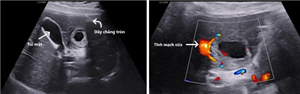

Thai ngoài tử cung mạn tính (TNTCMT) là một thể hiếm gặp của thai ngoài tử cung ở tai vòi

Tăng sinh mạch máu cơ tử cung - thông nối động tĩnh mạch mắc phải